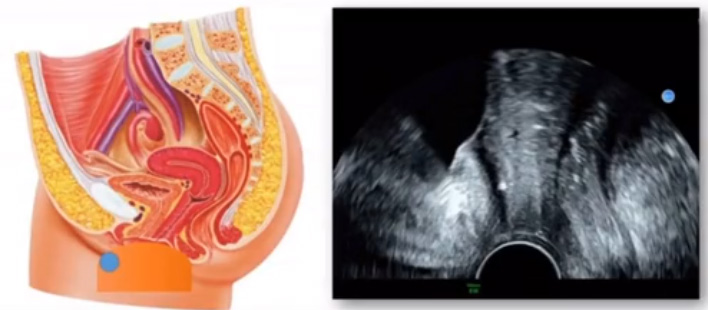

位于输卵管的后下方,子宫两侧的后上方;借卵巢系膜与子宫阔韧带后层相连。正常成人卵巢约4x3x2cm,跟睾丸的数值差不多,都是性器官,绝经后卵巢萎缩变小、变硬。所以绝经后妇女很难找到卵巢,主要功能:生殖和内分泌功能分泌性激素。女性的第二性征。女性内生殖器的血管分布,动脉有子宫动脉,卵巢动脉,阴道动脉,阴部内动脉。静脉它是与动脉伴行。重要了解的是子宫动脉,子宫动脉是髂内动脉前干的重要分支,妊娠时候血流速度会增加的,为无创性检查胎盘血管阻力的方法。未孕期频谱为高阻力低舒张波形;正常妊娠时血流速度增加,血流阻力下降。